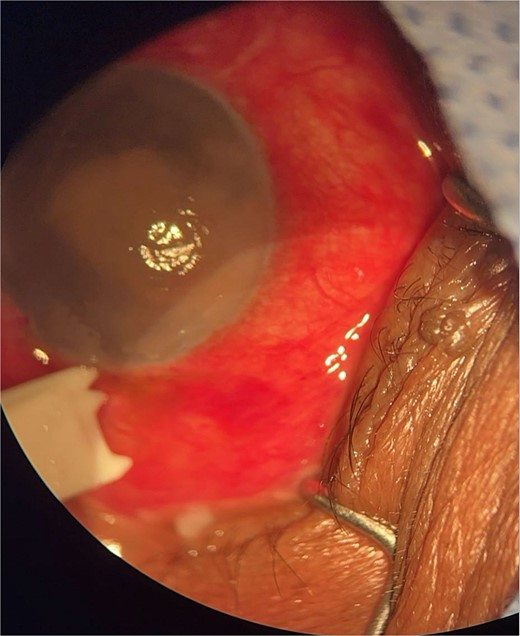

Patient 2: A 69-year-old Saudi female experienced severe right eye pain after surgery on the same day as patient 1. Visual acuity was reduced to hand motions, and examination showed conjunctival ciliary injection, corneal edema, and hypopyon (Fig. 3). B-scan confirmed vitritis (Fig. 4). She received similar emergency interventions as patient 1.

Surgical microscope examination showing hypopyon, chemosis, ciliary, and conjunctival injection in patient 2.